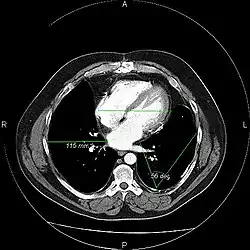

A picture archiving and communication system (PACS) is a medical imaging technology which provides economical storage and convenient access to images from multiple modalities (source machine types).[1] Electronic images and reports are transmitted digitally via PACS; this eliminates the need to manually file, retrieve, or transport film jackets, the folders used to store and protect X-ray film. The universal format for PACS image storage and transfer is DICOM (Digital Imaging and Communications in Medicine). Non-image data, such as scanned documents, may be incorporated using consumer industry standard formats like PDF (Portable Document Format), once encapsulated in DICOM. A PACS consists of four major components: The imaging modalities such as X-ray plain film (PF), computed tomography (CT) and magnetic resonance imaging (MRI), a secured network for the transmission of patient information, workstations for interpreting and reviewing images, and archives for the storage and retrieval of images and reports. Combined with available and emerging web technology, PACS has the ability to deliver timely and efficient access to images, interpretations, and related data. PACS reduces the physical and time barriers associated with traditional film-based image retrieval, distribution, and display.

Most PACS handle images from various medical imaging instruments, including ultrasound (US), magnetic resonance (MR), Nuclear Medicine imaging, positron emission tomography (PET), computed tomography (CT), endoscopy (ES), mammograms (MG), digital radiography (DR), phosphor plate radiography, Visible Light Photography (VL), Histopathology, ophthalmology, etc. Additional types of image formats are always being added. Clinical areas beyond radiology; cardiology, oncology, gastroenterology, and even the laboratory are creating medical images that can be incorporated into PACS. (see DICOM Application areas).